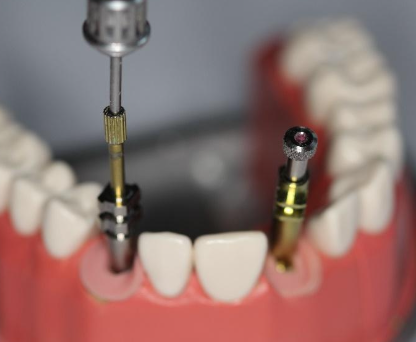

What are these?

Metal components, secured to implant using a metal threaded guide pin

What is this?

Plastic snap-on device

What is the purpose of the threads on the tip of the guide pin?

Secure the impression coping to the implant

Where are the flanges secured?

In the impression material, the guide pin is tightened to connect coping